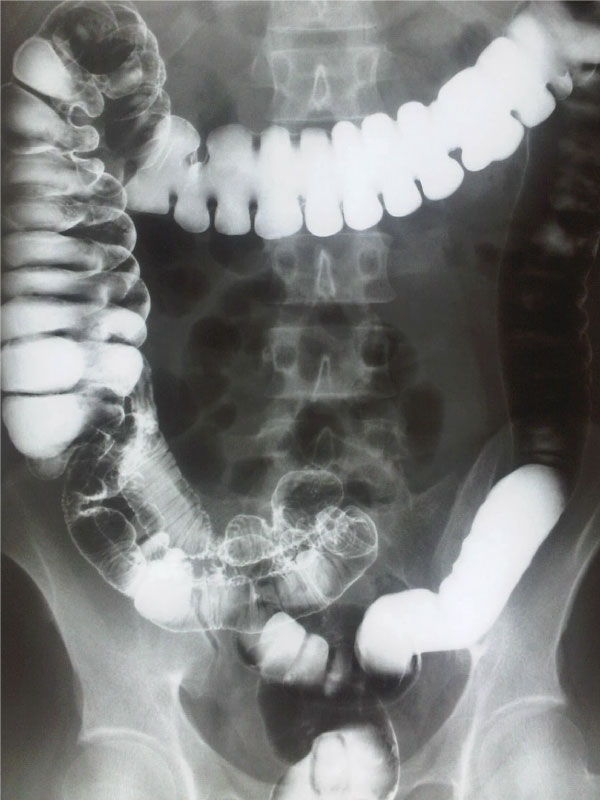

ESTUDIOS CONTRASTADOS

Examen de diagnóstico por imágenes que utiliza un medio de contraste, que es una sustancia especial la cual ayuda a mejorar la visibilidad de ciertos órganos, vasos sanguíneos o estructuras internas. Este tipo de estudios nos permiten obtener imágenes mucho más detalladas del sistema digestivo, urinario, vascular, entre otros. Lo cual nos ayuda a detectar obstrucciones, tumores, inflamaciones o malformaciones.

Dependiendo el tipo de estudio y sus necesidades.

El contraste puede aplicarse vía oral, rectal o intravenoso.